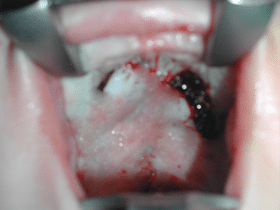

Ambdues solapes es suturen i es tornen a allargar el vel

Fissura palatina: resultat a la fi de la cirurgia | Fissures Palatines i Llavi Leporí

Paladar facial al final de la cirurgia